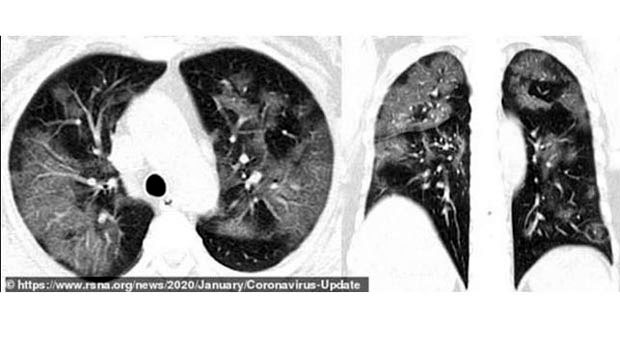

Snimci CT skenera 54-godišnje žene koja je dobila virus nakon putovanja u Vuhan pokazuju delimično ispunjene vazdušne prostore. Ženi je dijagnostikovana teška upala pluća uzrokovana virusom, a imala je simptome kašlja, groznice, umora i kongestije grudnog koša. Ljekari su joj davali kiseonik i antibiotike.